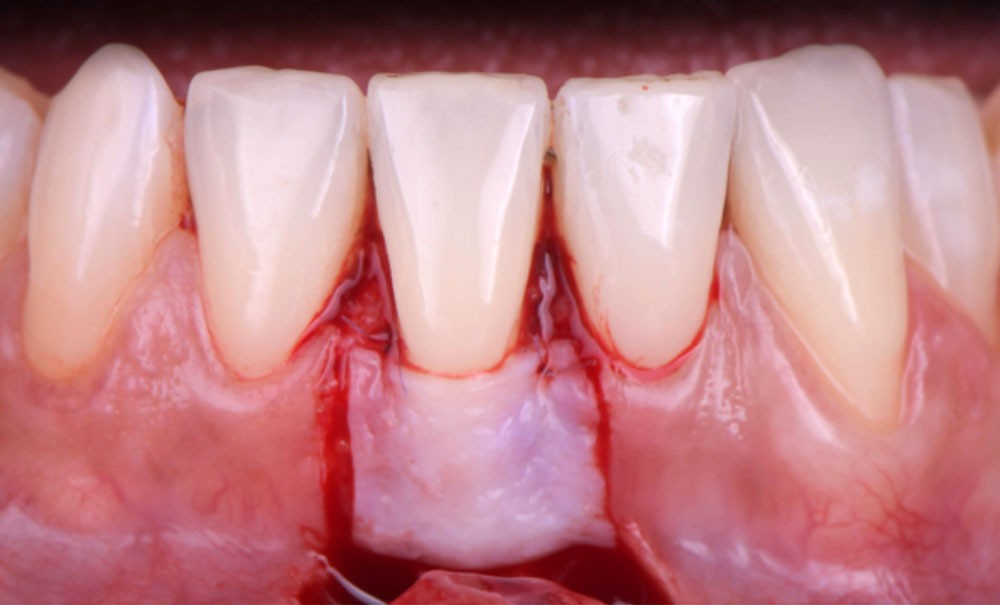

Le lambeau positionné coronairement associé à une greffe de conjonctif enfoui (fig. 1-4)

La stabilité du lambeau est primordiale dans la réussite de cette technique de recouvrement. En cas d’instabilité, même en l’absence d’erreurs techniques, l’analyse de certains facteurs liés au patient est indispensable. Afin de maintenir la stabilité du lambeau jusqu’à la dépose des points, le praticien doit veiller à l’adéquation du contrôle de plaque effectué par le patient, à l’absence de mastication impliquant la zone d’intervention, à la prévention de tout traumatisme ou de modifications des conditions locales par le patient.

Selon le Dr Sylvie Pereira, contrairement au maxillaire où la hauteur du lambeau déplacé coronairement est déterminée par la profondeur de la récession, à la mandibule, les incisions horizontales sont placées de manière à obtenir au moins 2 mm de tissu…